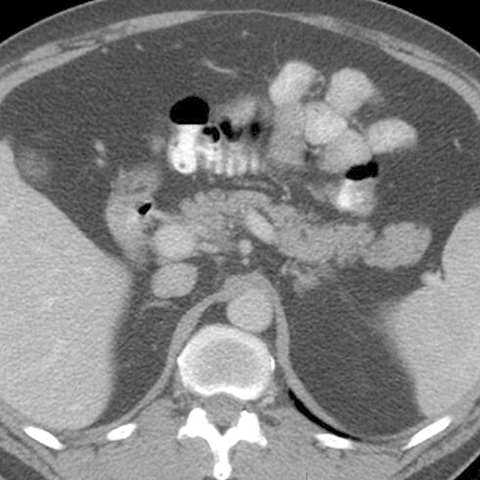

Normal Pancreas, Axial CT [4 of 5]